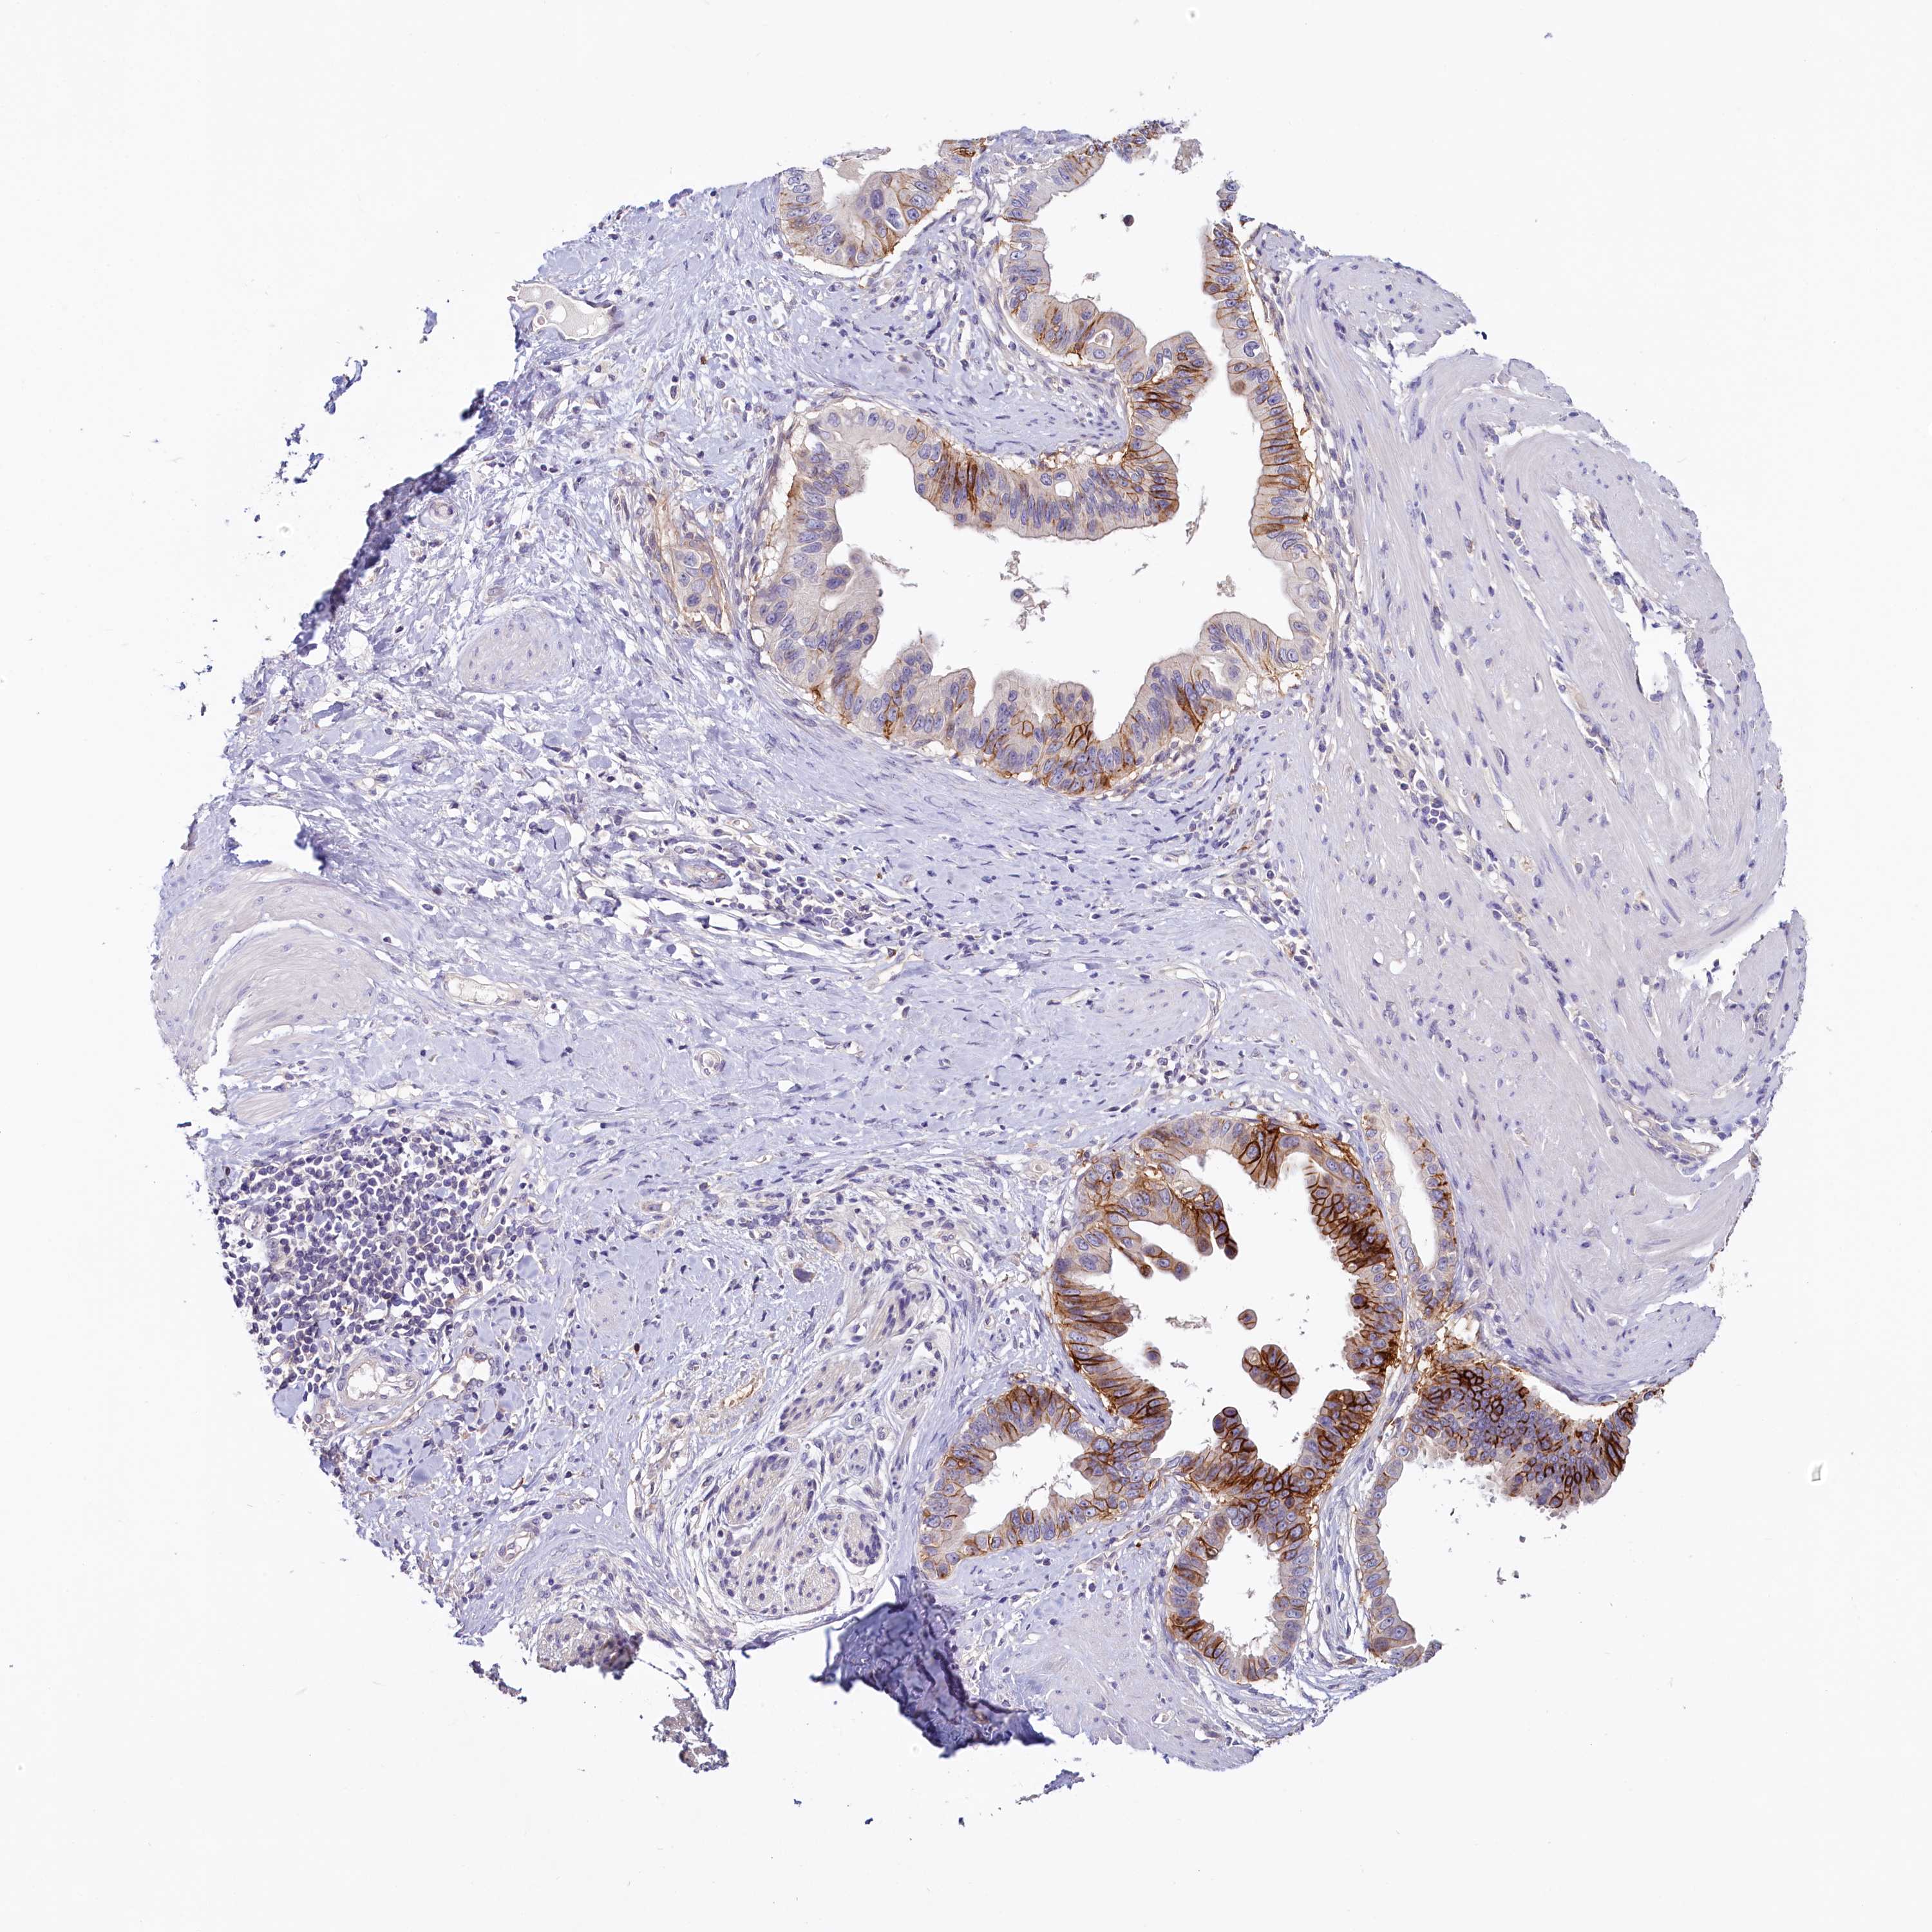

PANCREATIC CANCER - Protein expressioni

A mouse-over function shows sample information and annotation data. Click on an image to view it in a full screen mode. Samples can be filtered based on level of antibody staining by selecting one or several of the following categories: high, medium, low and not detected. The assay and annotation is described here.

Note that samples used for immunohistochemistry by the Human Protein Atlas do not correspond to samples in the TCGA dataset.

Antibody stainingi

Antibody staining in the annotated cell types in the current human tissue is reported as not detected, low, medium, or high, based on conventional immunohistochemistry profiling in selected tissues. This score is based on the combination of the staining intensity and fraction of stained cells.

Each image is clickable and will lead to virtual microscopy that enables deeper exploration of all samples and also displays staining intensity scores, fraction scores and subcellular localization as well as patient and tissue information for each sample.

Antibody HPA037433

Antibody HPA037434

Staining

High

Medium

Low

Not detected

Intensity

Strong

Moderate

Weak

Negative

Quantity

>75%

75%-25%

<25%

None

Location

Nuclear

Cytoplasmic/membranous

Cytoplasmic/membranous,nuclear

Adenocarcinoma, NOS